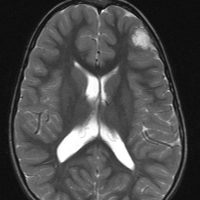

局所照射後の白質変性,脳質壁の白質変性

全脳照射でなくても局所照射でも放射線治療後には白質変性が生じます。無症状のことが多いですが,照射野内の脳萎縮などを伴うと高次脳機能障害などの症状をだすことはあります。

この患者さんは右前頭葉のびまん性星細胞腫に46グレイ23分割という低い線量の局所照射をしました。放射線治療8年後のMRI FLAIR画像です。腫瘍の再燃はなく,脳室周囲の白質が高信号になっています。脳梁や透明中隔の白質組織も高信号になり,非常に軽度の白質変性を示しています。でも,何の症状もありません。注意しなければならないのは,この所見を星細胞腫の再発あるいは進行と捉えて余分な治療をしないようにすることです。とくにグレード2の星細胞腫と乏突起膠腫の時に問題となります。